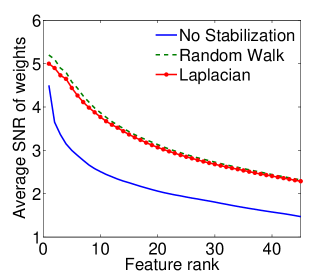

|

|

| (a) Cumulative, | (b) Stagewise (Shared), |

|

|

| (c) Stagewise (Separate), | (d) Stagewise (Separate), |

We now examine the models stability against data sampling and evaluate the stabilizing property of the proposed method (Sec. 6.2). For each fold, we generated samples, each of which was drawn randomly from % of training data. Each example resulted in a model, and the feature weights were recorded and finally the results of all folds – models – were combined. Figs. 5(a–d) show the indices (Eq. (5)) as functions of the rank list size , for all ordinal classifiers. The instability is clearly an issue – the average selected probability drops as more features are included. Using both the Laplacian and random walk regularization methods (Eqs. (9,10)), the improvement in stability is evidenced in all settings. The instability and stabilizing effect were similarly obtained with the indices (Figs. 6(a–d)).